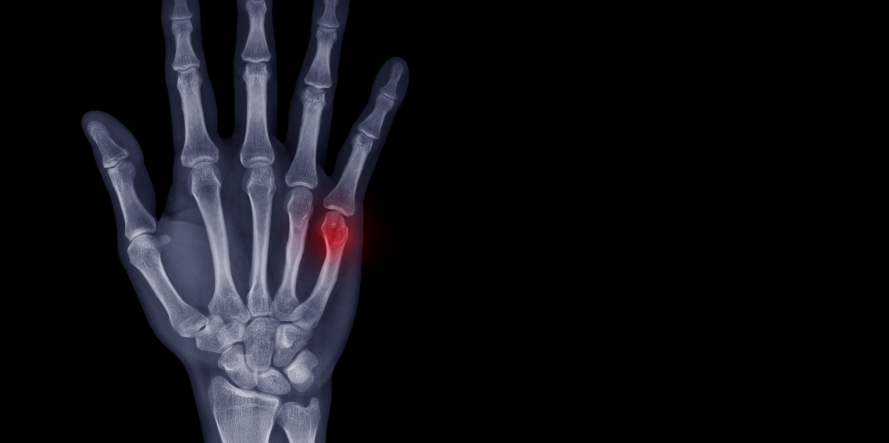

Κάταγμα Μετακαρπίου

Τα κατάγματα των μετακαρπίων αντιπροσωπεύουν έναν από τους πιο συχνούς ορθοπεδικούς τραυματισμούς στην περιοχή του χεριού. Τα συγκεκριμένα κατάγματα είναι συνήθως αποτέλεσμα άμεσου τραύματος σε ένα από τα πέντε μετακάρπια οστά ιδίως σε αθλητές αθλημάτων επαφής ή λόγω χτυπήματος σε σκληρές επιφάνειες.

Κάταγμα Μετακαρπίου – Διάγνωση του κατάγματος

Η διάγνωση του κατάγματος πραγματοποιείται με ακτινογραφία. Ένα πλήρες ιστορικό θα πρέπει να λαμβάνεται από τον ασθενή με ιδιαίτερη εστίαση στον τρόπο που πραγματοποιήθηκε ο τραυματισμός, το χρονικό πλαίσιο μέσα στο οποίο συνέβη, και σε προηγούμενες χειρουργικές επεμβάσεις του χεριού ή άνω άκρου.

Μια ενδελεχής φυσική εξέταση είναι απαραίτητη για την εκτίμηση της παρουσίας στροφικής παραμόρφωσης, η οποία σε πολλές περιπτώσεις δεν αποτυπώνεται με απλές ακτινογραφίες.